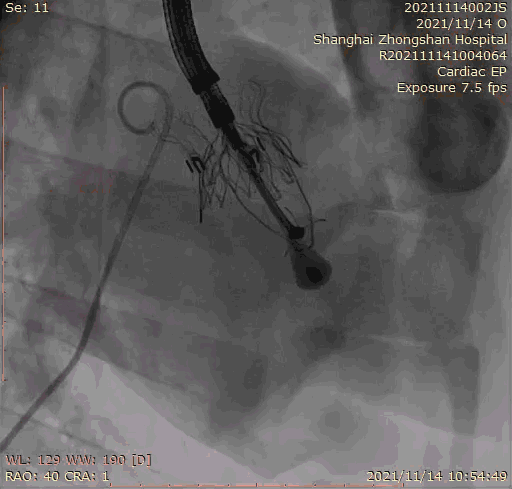

本次臨床前研究經右側頸靜脈置入LuX-Valve Plus輸送系統可調彎鞘管,在DSA及超聲引導下將人工三尖瓣瓣膜植入到原有三尖瓣位置,利用獨特的錨定技術將人工瓣膜支架可靠固定在預定的位置。